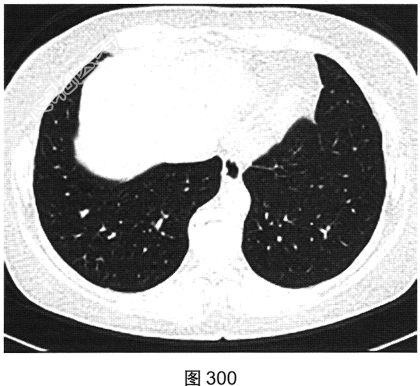

- 多项选择题3.[提示]HRCT图像如图298~图301所示。从患者的HRCT图像中可见哪些阳性征象( )

A、双侧腋窝及纵隔内多发增大淋巴结

B、双肺多发薄壁透亮影

C、小叶间隔增厚

D、右肺多发钙化结节灶

E、双肺多发磨玻璃样密度影

F、支气管扩张